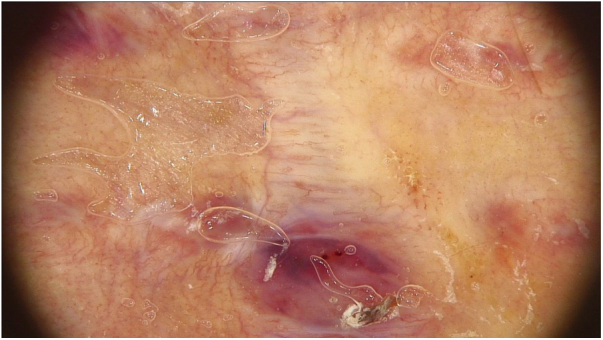

Figure 1.

The dermoscopic image of the first scar. The polymorphic pattern with a predominance of linear irregular vessels was visible.

Clinical examination of the red scar revealed the presence of the shining nodule in its lower segment. In dermoscopy, the polymorphic pattern was present with a predominance of linear irregular vessels (Fig. 1). Considering dermoscopic features and the diagnosis of Spitz nevus, the patient underwent subsequent excision of the scar and histopathological diagnosis of recurrent Spitz nevus was established.